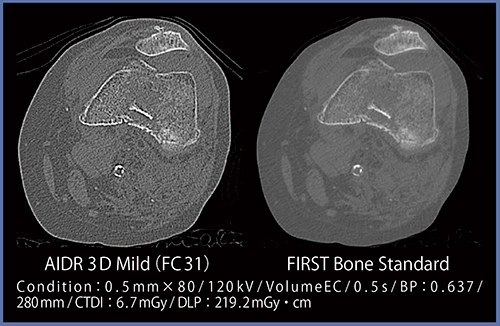

●症例3:踵骨骨折

図4では,AIDR 3Dで見られるアンダーシュートがFIRSTで低減している。このため,FIRSTでは海綿骨の骨折線(←)が同定しやすくなっている。

図4 症例3:踵骨骨折